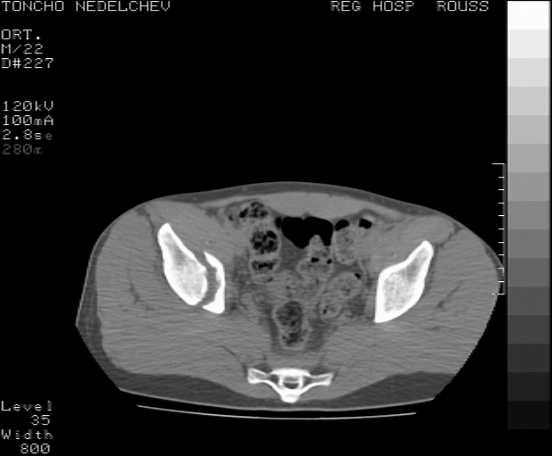

[Ortho] Acetabular fracture

Here are some more axial images. What is your opinion as for the timing of the operative treatment?